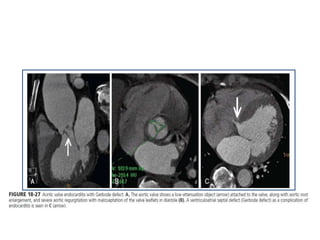

• ANATOMIC EVALUATION OF CARDIAC VALVES and their motion also

is feasible for both native and prosthetic valves.

• Aortic stenosis is characterized by CT in terms of both the extent of valvular

calcification and orifice area by planimetry.

• In AORTIC REGURGITATION, malcoaptation of the valve

leaflets by greater than 0.75 cm2 is associated with severe

aortic regurgitation .

• Prosthetic valve malfunction including size mismatch, tissue

ingrowth, or valve thrombosis can be identified.

• Increasingly, cardiac CT imaging in patients with prosthetic

valve endocarditis identifies paravalvular leaks , and can

provide a preoperative coronary arteriographic assessment

when cardiac surgery is anticipated.